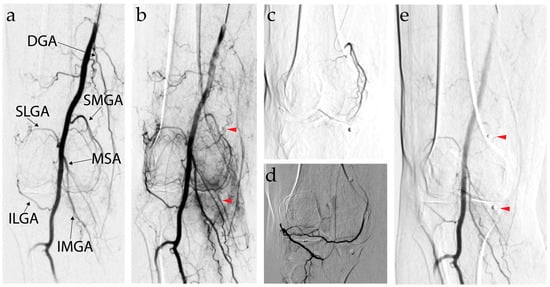

7.3. Genicular Artery Embolization Technique

7.4. Complications of Genicular Artery Embolization